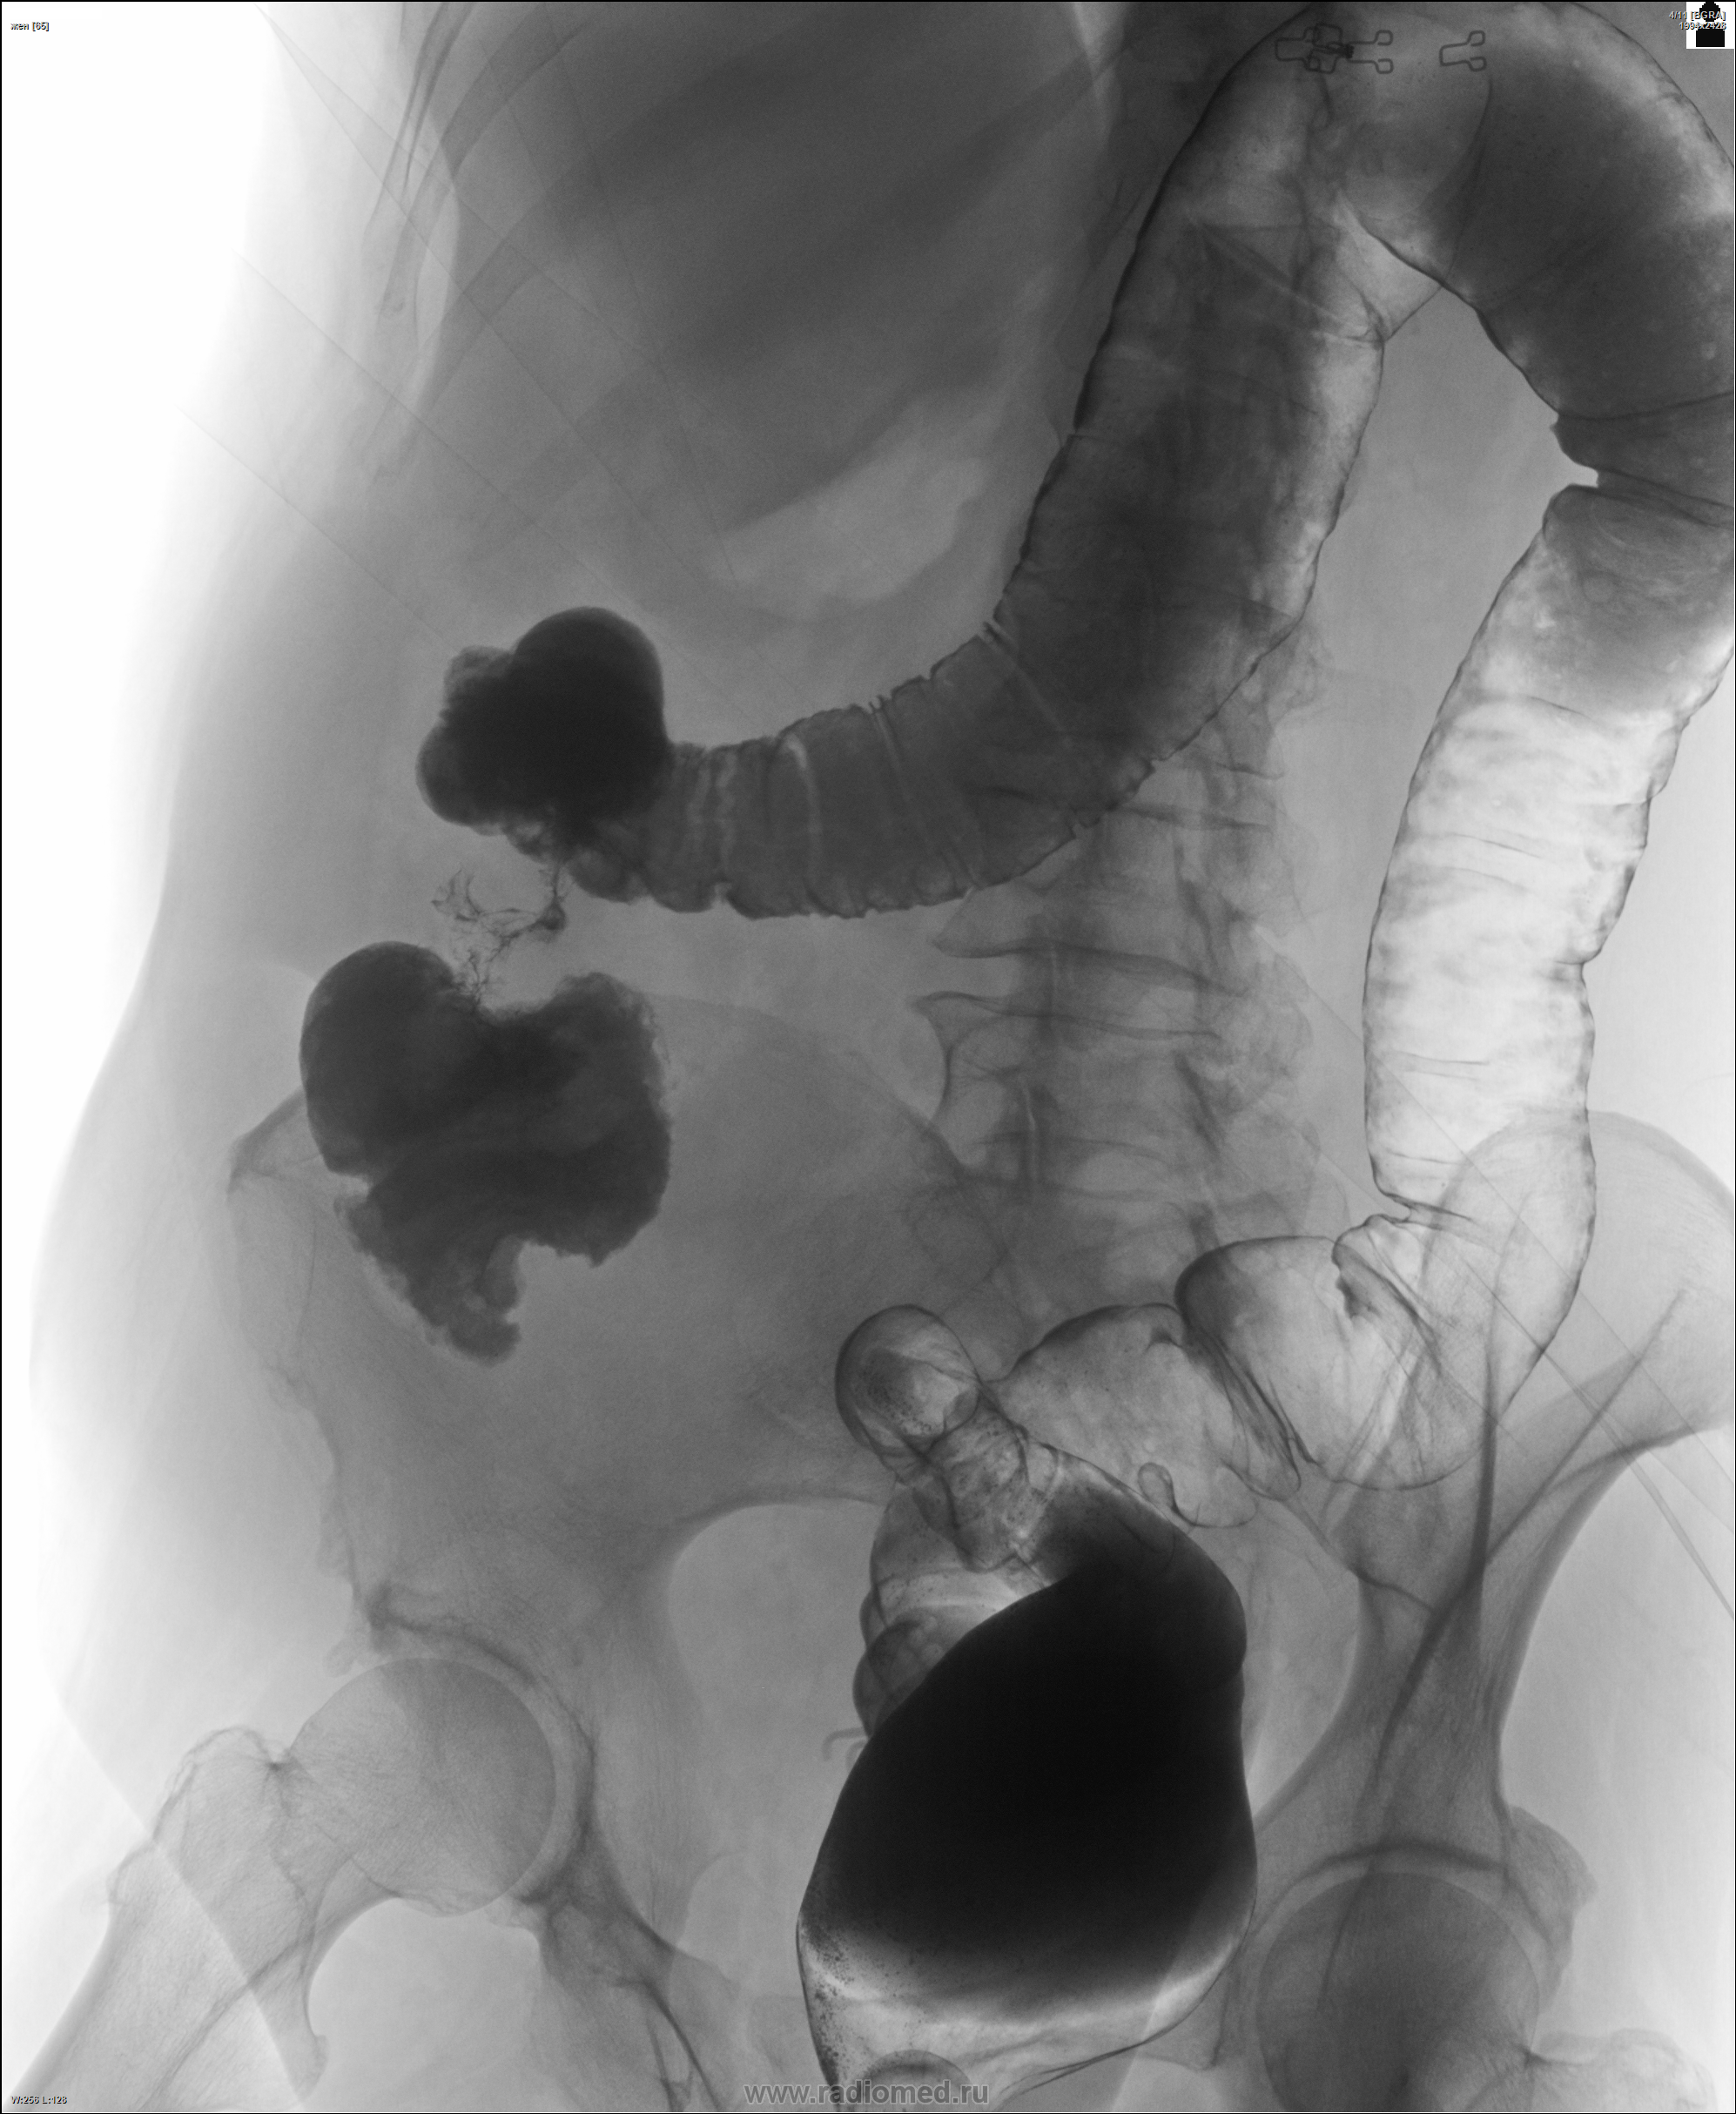

Рентгеноконтрастные Исследования Кишечника: Визуализация и Методики